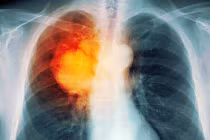

| Công ty dược phẩm của Đức Merck KGaA sẽ tiến hành một thử nghiệm mới cho loại vắc-xin ung thư phổi của họ. |

Merck KGaA cho biết, công ty họ sẽ tiến hành kiểm tra loại thuốc trước đó có tên là Stimuvax và hiện được gọi là Tecemotide trên bệnh nhân đã được điều trị bằng cả hóa trị và xạ trị đồng thời, trong một giai đoạn đầu của quá trình điều trị.

Chẳng hạn như lần thử nghiệm đầu tiên của loại vắcxin ung thư phổi Tecemotide được thực hiện trước đó đã không thể cung cấp bằng chứng rõ ràng về việc cải thiện tỷ lệ sống cho bệnh nhân của thuốc. Trong thử nghiệm này, có cả sự tham gia của những bệnh nhân đã được cho hóa trị và xạ trị riêng.

Công ty này cho biết, khoảng 1.000 bệnh nhân sẽ tham gia trong thử nghiệm mới, được gọi là START2, ít người hơn so với 1.200 người tham gia trong thử nghiệm START trước đó.

Thuốc mới này, được cấp phép bởi công ty công nghệ sinh học Mỹ Oncothyreon, sẽ được thử nghiệm trên bệnh nhân ung thư phổi không phải tế bào nhỏ (NSCLC) tiến triển ở giai đoạn III. Những bệnh nhân này được cho dùng thuốc bởi họ đều không thể phẫu thuật cắt bỏ khối u mà phải kết hợp hóa trị và xạ trị, công ty cho biết.